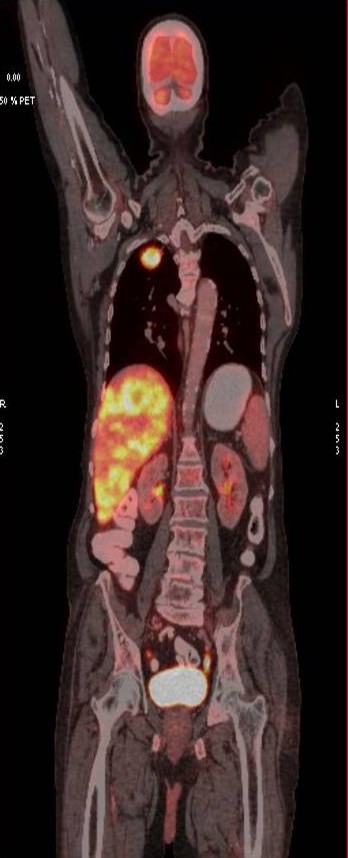

CT scan of the abdomen confirmed the findings ; For further clarification PET whole body scan was done at a centre in Chennai. The following images are from that.

Heterogeneously enhancing irregular spiculated soft tissue mass measuring ~ 34 x 29 mm noted in the apical segment of right upper lobe. The lesion abuts the pleura posteriorly.

FDG avid enhancing lymph nodes noted in right and left paratracheal regions, largest measuring ~ 19 x 11 mm on the right side.

- Metabolically active spiculated right upper lobe lung mass – likely malignant primary.

Mediastinal and retroperitoneal FDG avid metastatic lymphadenopathy.

Extensive FDG avid hepatic metastases involving both lobes.

Focal FDG avid lesion in left lamina of D10 – possibly metastatic.